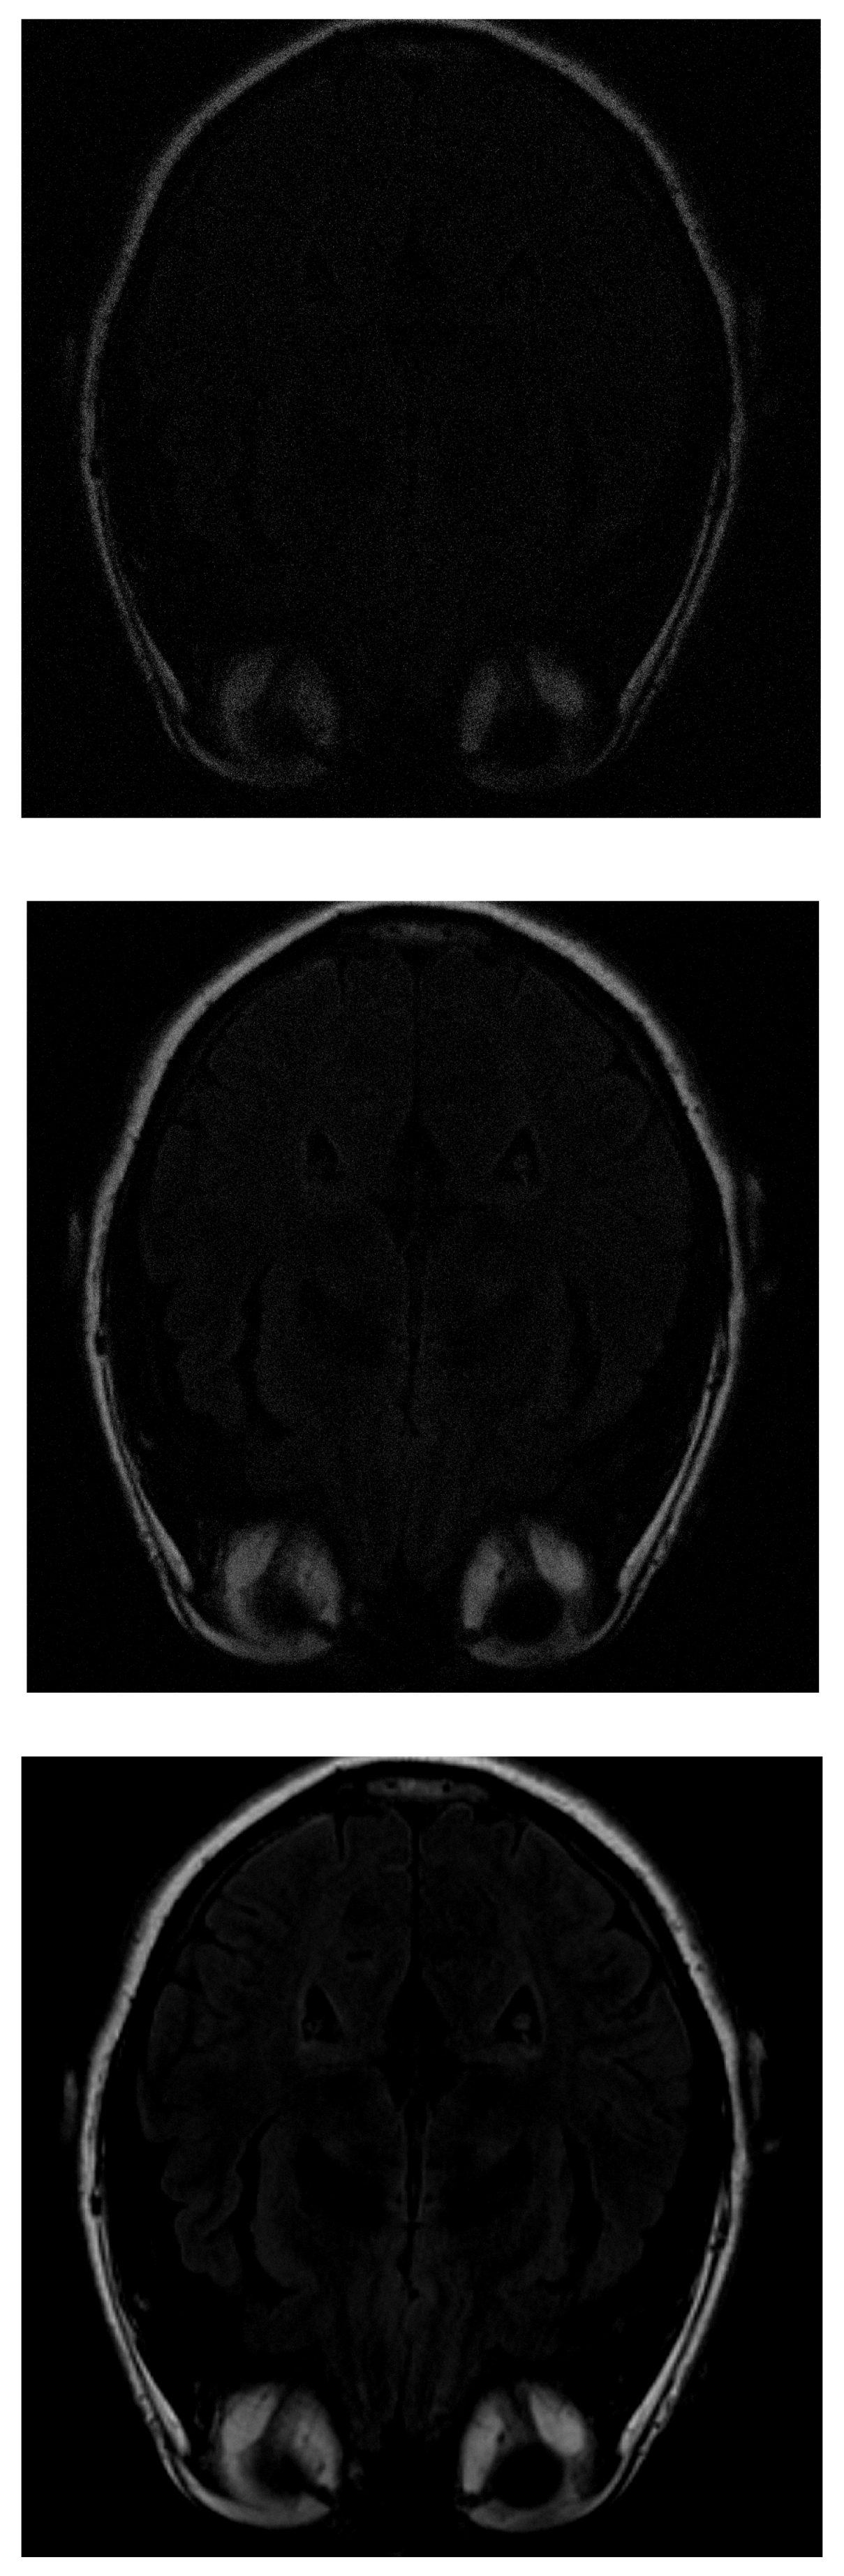

One of the images used in the simulations is shown in Figure 3. The image corresponds to an axial section of the brain in the plane marked by the blue lines in Figure 4. In it, the orbit of the eyes can be distinguished in the lower part. Fat appears with a very strong signal, while water and cerebrospinal fluid have a very low intensity.

Figure 3.

MRI image of an axial slice of the brain. In the area below are the eye orbits [15].

In the IRLS reconstruction, only the shape of the head and the orbits are detected in the first measurements, while the white matter is not distinguishable (Figure 5 top). When 70% of the data is available (Figure 5 middle), the white matter can be distinguished but with little intensity. When the intensity of the orbits increases, the effect of the artifact begins to be noticed. If the algorithm is run with all available data (Figure 5 bottom), the edge resolution is increased, but white matter signal intensity is lost. That makes their identification more difficult.

Figure 5.

Reconstruction of the image in Figure 3 using IRLS with (top), (middile) and (bottom) of taken measurements.